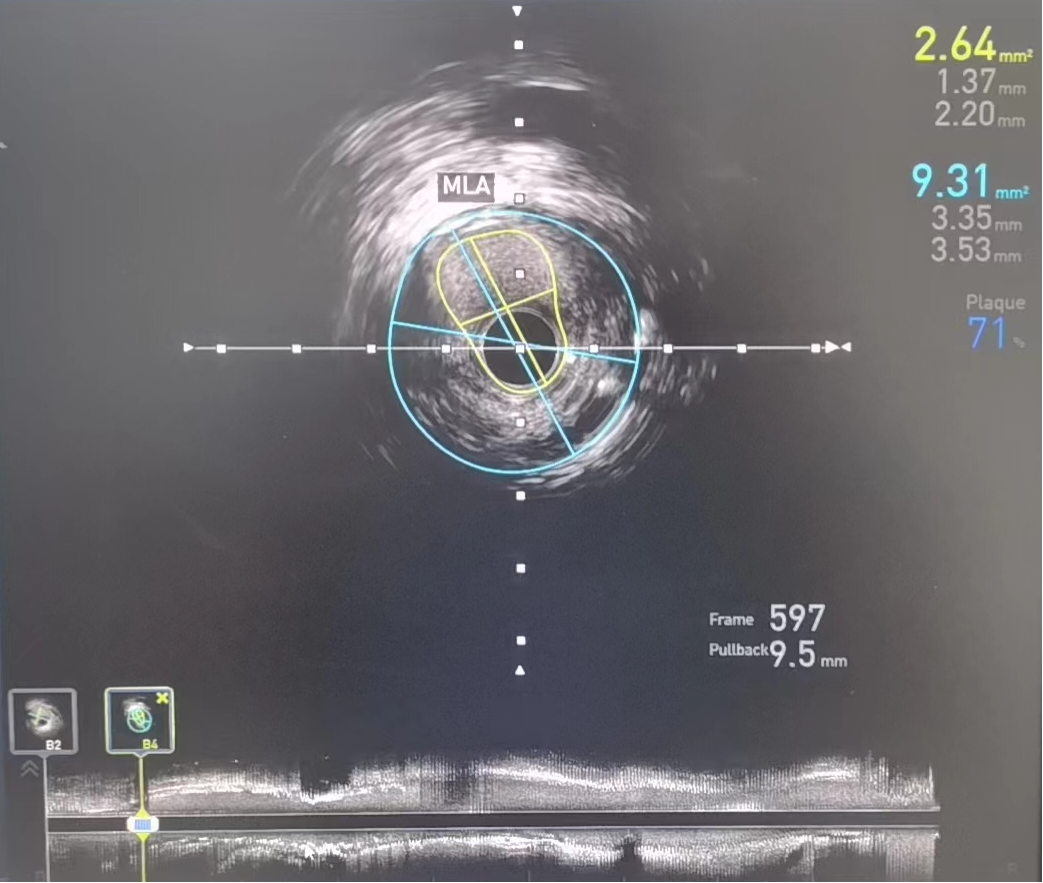

术前:IVUS-前降支管腔中段严重狭窄,最小管腔面积仅2.64mm2

IVUS检查提示右冠中段支架以远病变加重,右冠原支架管腔畅通,经IVUS测量得出病变处MLA(管腔最小横截面积)2.64mm2,结合心电图缺血判断,该病变为患者心绞痛发作罪犯病变,对病变处实施介入治疗。

考虑无法使用造影剂进行支架定位,如何将支架定位到理想的位置,成为手术的最大难点。专家团队应用血管内超声的换能器作为路标,精确测量所需支架长度及直径,在透视下,完美将支架释放于理想位置,于右冠顺利植入支架与原有支架串联。“打通”了冠脉狭窄通路,实现了右冠脉血运的重建,再次复查IVUS显示支架位置完美,膨胀、贴壁良好,病变被完全覆盖且左冠病变无进一步处理指征,全程未使用造影剂,恢复良好。